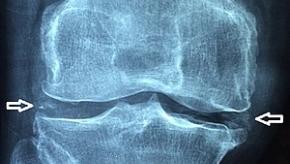

Read ArticleChondrocalcinosis Increases Osteoarthritis Risk

Analysis of data from two large, prospective cohort studies show that knee chondrocalcinosis was associated with an increased risk of incident knee osteoarthritis.